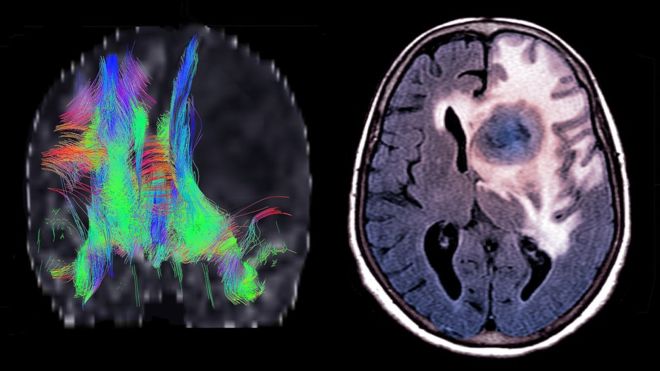

أعرب عدد من العلماء عن تفاؤلهم بشأن إيجاد علاج محتمل لمساعدة الأشخاص المصابين بسرطان المخ غير القابل للشفاء.

وخضع عشرة مرضى حتى الآن في بريطانيا للعلاج الجديد، وهو عبارة عن فيروس يسبب أعراضا تشبه أعراض الأنفلونزا المتوسطة.

وأشارت دراسات أولية إلى أن الفيروس يمكنه أن يعبر حاجز الدم في المخ، وقد يساعد في "تشغيل" أنظمة المناعة في الجسم لمهاجمة الورم.

ويقول الباحثون إن الفيروس، ويسمى الفيروس الريبوزي، يتجه إلى إصابة الخلايا السرطانية، ويترك إلى حد كبير الخلايا السليمة وحدها.

وحتى الآن اعتقد العلماء أنه من غير المرجح أن يتمكن الفيروس من العبور من الدم إلى المخ، بسبب الغشاء الواقي الذي يحيط بالدماغ، والمسمى حاجز الدم في الدماغ.

وثبت، في أول مريض يجري تجربة العلاج عليه، أن الفيروس عبر بنجاح ووصل إلى هدفه.

وكشف تحليل لعينات من الورم أن الفيروس ساعد على تنبيه وحشد النظام المناعي للجسم، لمهاجمة الأنسجة السرطانية.